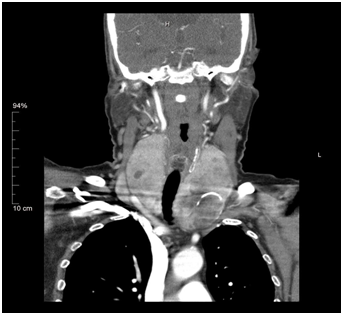

Cross sectional imaging modalities are not indicated in the vast majority of thyroid nodules. CT scan are usually considered in patients with suspected tracheal compression, retro-sternal extension and lung metastasis in cases of malignant nodules. A full body CT scan is indicated in patients with primary or secondary lymphoma of thyroid to stage the disease (Figure 2-4). MRI scans are indicated in cases of thyroid nodules presenting with palpable lateral compartment neck nodes.

Figure 2 CT Axial view - calcification and tracheal compression.

Figure 3 CT Coronal view - tracheal compression.